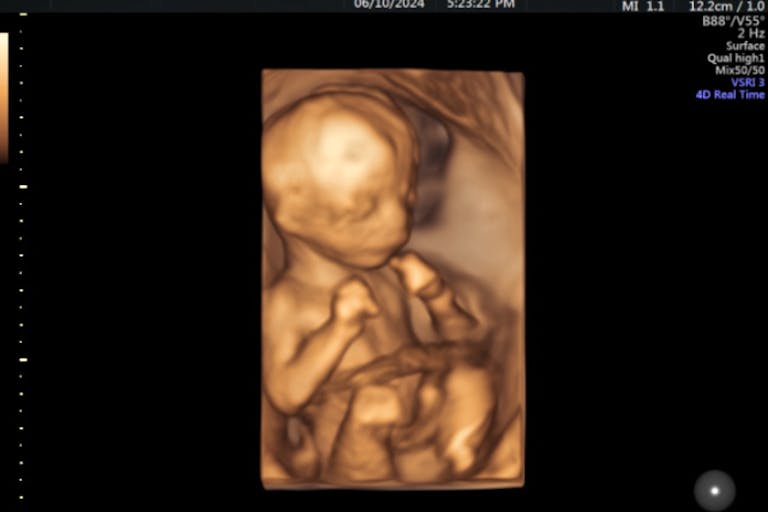

As you can see in this image published on Planned Parenthood’s website (fetal development page separate from the corporation’s abortion page), babies at 13 weeks and older are more developed.